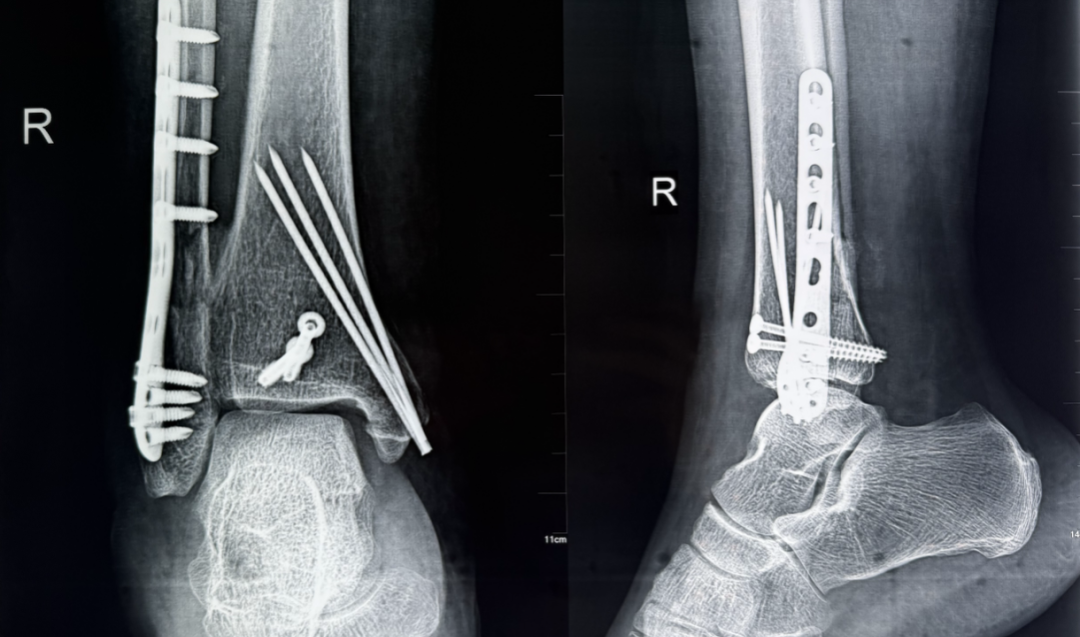

术后

无影灯下,一场与时间的赛跑紧张进行。梁西兴凭借精湛的技术,在严重关节畸形与脆弱的软组织条件下精准操作,实现碎骨复位的同时,以最小创伤完成了稳固固定。从决定手术到顺利完成还不到3小时,为患者赢得了良好恢复时机。